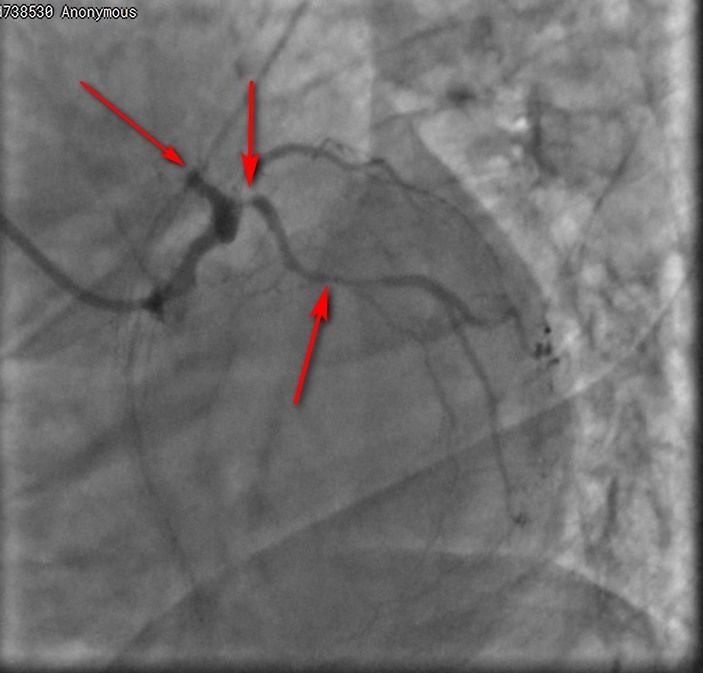

Один из показательных примеров. Пациентка с сахарным диабетом, обратилась с незаживающей язвой на стопе и болью (синдром диабетической стопы).

После обследования искренне удивилась, что у нее есть признаки поражения сосудов сердца – оно же ее не беспокоило. Мы получили объективные данные – ЭКГ, ЭХО-КГ, поэтому настояли и сделали коронарографию – исследование сосудов сердца. Все основные артерии, кровоснабжающие сердце, критически сужены (поражения показаны стрелками). Такой пациент имеет шансы умереть в любую минуту. Тем более – во время любого вмешательства или операции (в том числе – по время высокой ампутации, если такому пациенту она выполняется, что не редкость, к сожалению).